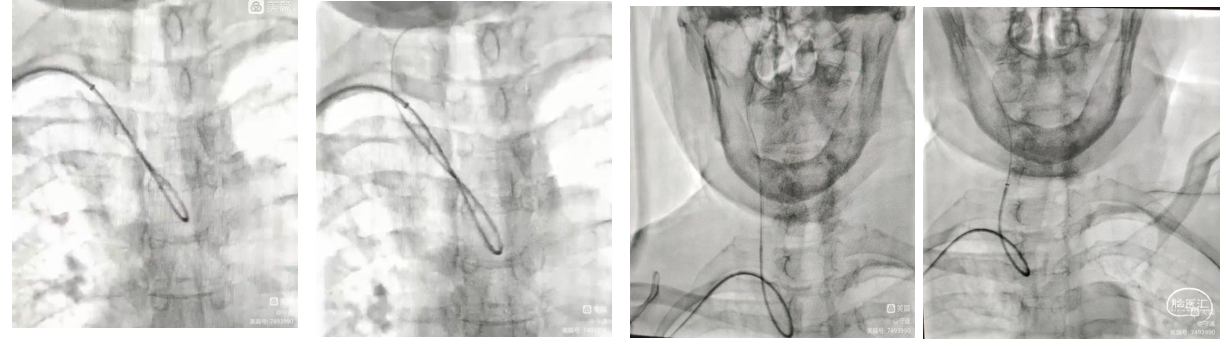

1、置入7F薄壁桡动脉鞘。

2、260cm 035in亲水泥鳅导丝携带4F 140cm西蒙导管外衬7F-105cm赛诺远端通路导管超选右侧颈总动脉建立血管介入通路。

通路建立:经右侧桡动脉近桡穿刺置入7F薄壁桡动脉鞘。

弓型及导丝导管到位操作简述:

III主动脉弓,260cm 035in亲水泥鳅导丝携带4F 140cm西蒙导管外衬7F-105cm赛诺远端通路导管超选右侧颈总动脉建立血管介入通路。

重要操作简述:

4F sim2 造影导管超选右侧颈总动脉后会拉导管进入颈总动脉远端,沿sim2造影导管推送泥鳅导丝至颈内动脉C1段,固定泥鳅导丝和sim2造影导管,推送赛诺远端通路导管通过颈总动脉起始部环形部位顺利到达颈内动脉C2段;撤出泥鳅导丝和sim2造影导管。